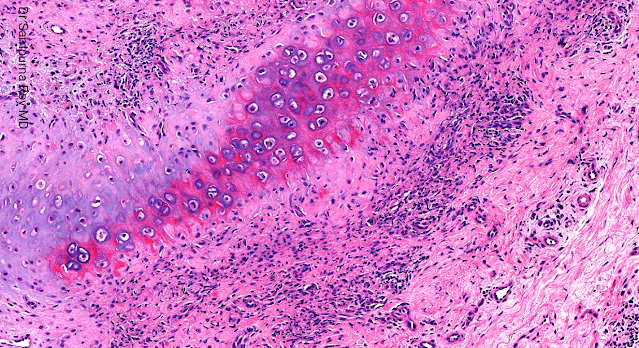

Dermatopathology Case 196 Get link Facebook X Pinterest Email Other Apps April 12, 2022 A 50-year old female presented with pain, redness, and swelling of her right ear. Answer Get link Facebook X Pinterest Email Other Apps Comments